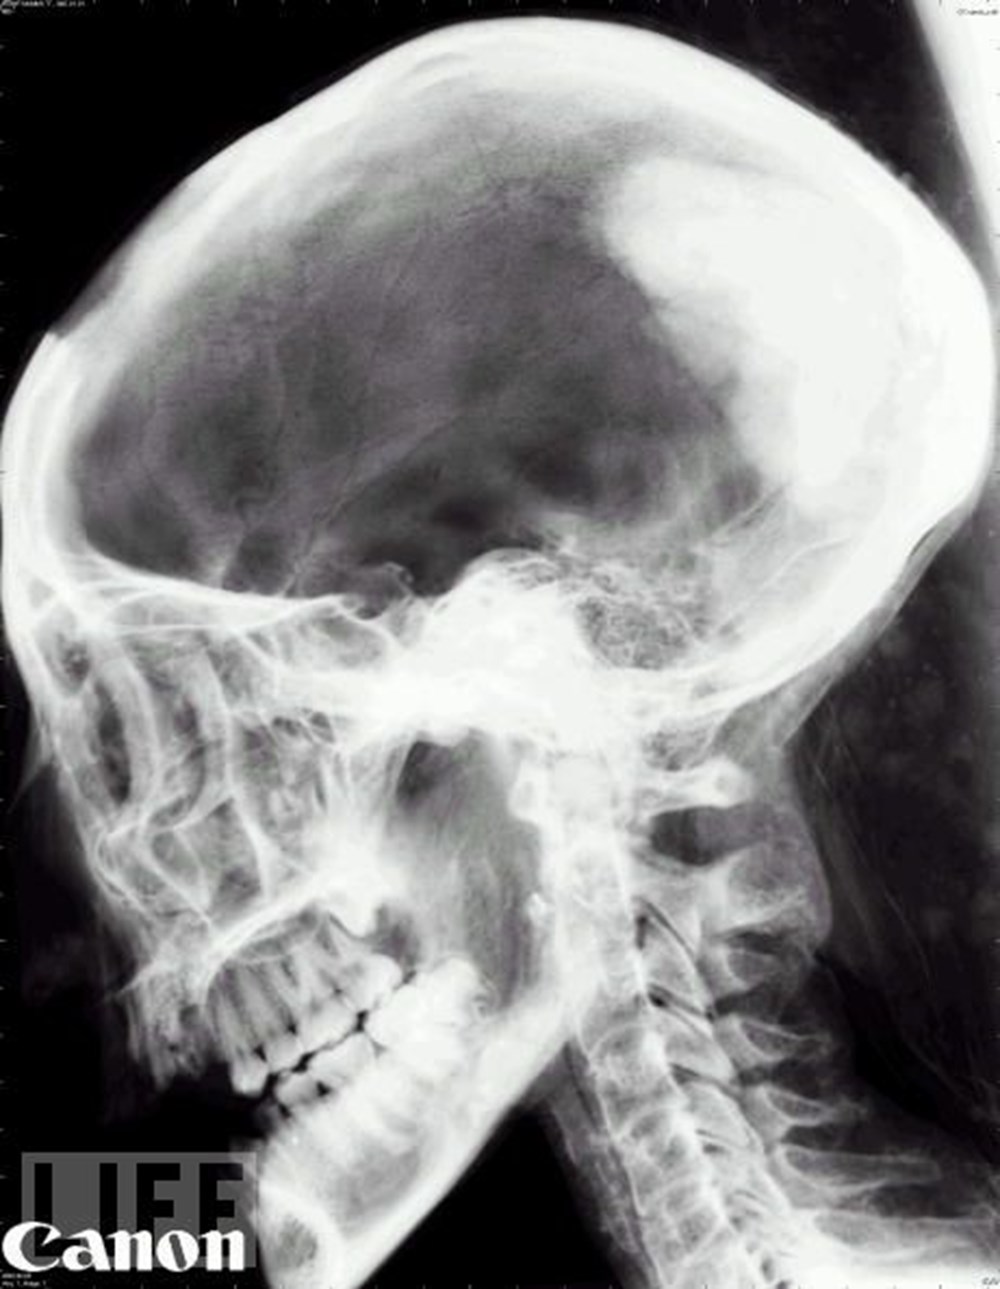

Hayatın röntgeni NTV From Pinterest

Hayatın röntgeni NTV From Pinterest

Hayatın röntgeni NTV

Hayatın röntgeni NTV

Hayatın röntgeni NTV

Hayatın röntgeni NTV

Hayatın röntgeni NTV

Hayatın röntgeni NTV

Hayatın röntgeni NTV

Hayatın röntgeni NTV

Boyun Röntgeni Neden Boyun Röntgeni Çektirmeliyim

Hayatın röntgeni NTV

Hayatın röntgeni NTV

Hayatın röntgeni NTV